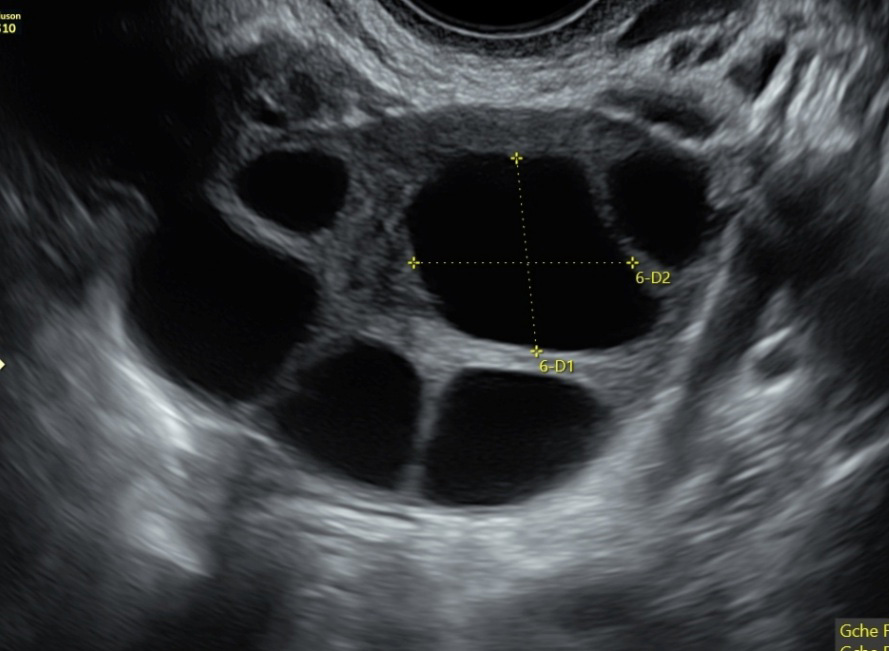

Échographie de procréation médicalement assistée

Vous pouvez faire réaliser au cabinet vos échographies de monitorage folliculaire et mesure de l’endomètre pour tous les types de PMA : stimulation ovarienne, insémination intra-utérine et fécondation in vitro, que vous soyez suivie en France (à Brest, Rennes ou Nantes par exemple) ou à l’étranger. Une ordonnance du centre de PMA est nécessaire.